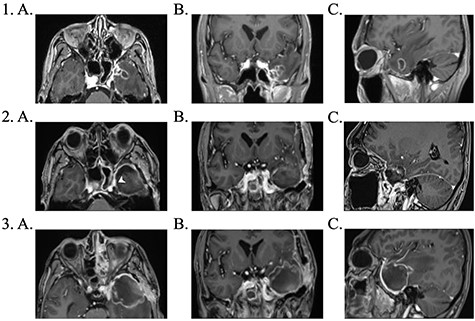

1. Pre-operative contrast enhanced brain MRI: (a) T1 axial view with enhancing lesion; (b) T1 coronal and (c) T1 sagittal. 2. First post-operative contrast enhanced brain MRI showing resection of lesion: (a) T1 axial. Arrow: dural enhancement of sphenoid sinus; (b) T1 coronal and (c) T1 sagittal. 3. Second post-operative contrast enhanced brain MRI following endoscopic re-resection: (a) T1 axial; (b) T1 coronal and (c) T1 sagittal.

The patient underwent a left-sided temporal lobectomy to excise the lesion but, due to the proximity to the cavernous sinus, the lesion was not followed beyond the dural attachment on the middle fossa floor. Unexpectedly, the histopathology revealed hyphae resembling a zygomycete, with broad (5–12 μm) hyphae without septae and branching angles between 45° and 90° (Fig. 2). Liposomal amphotericin B treatment was initiated at 5 mg/kg per day and later increased to 10 mg/kg per day. Fungal cultures yielded no growth.